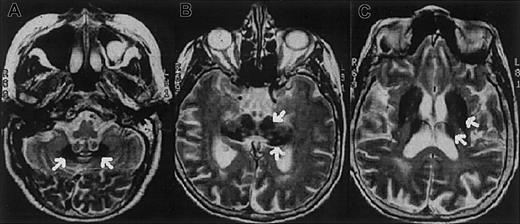

The proband is a 62-year-old Italian woman. No family history of diabetes, iron overload, anemia, or neurologic disorders was recorded. At age 38 years the patient developed insulin-dependent diabetes mellitus. A mild degree of anemia (hemoglobin 9.1 g/L) with normal mean corpuscular volume (MCV; 86 fL) and low-normal values of mean corpuscular hemoglobin (MCH; 27.2 pg) and mean corpuscular hemoglobin concentration (MCHC; 31.7 g/dL) was documented at age 51 years. Serum iron concentration was 33 μg/dL, transferrin saturation 12%, and serum ferritin 819 μg/L. Bone marrow aspirate revealed mild dyserythropoiesis; iron staining showed abundant iron in RE cells and absence of iron granules in erythroblasts. Moderate anemia and abnormal iron parameters without evidence of blood losses or inflammatory diseases were regularly observed at follow-up. Ataxia, dystonia, mild parkinsonism, and dementia became evident at the age of 62 and progressed rapidly. Magnetic resonance imaging of the brain showed a paramagnetic deposition in the basal ganglia, dentate nucleus, thalamus, substantia nigra, and cerebral and cerebellar cortex (Figure1). Serum Cp was undetectable. Liver function tests were normal. No Kayser-Fleischer ring was observed, but the retina showed a pigmentary degeneration.

Axial T2-weighted magnetic resonance images of the proband's brain show low-signal areas (arrows) in the dentate nucleus (A), red nucleus and substantia nigra (B), and corpus striatum and thalamus (C), which suggest iron deposition in these regions.